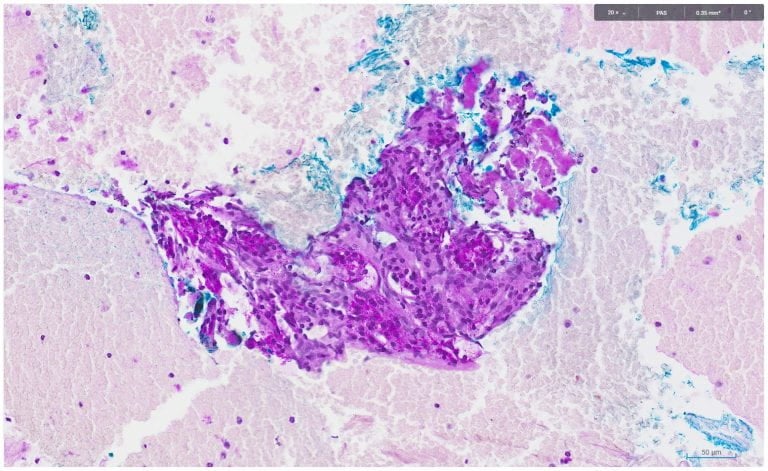

PAS and DPAS staining showed the following:

The overall cyto-histo-morphology and immuno-histochemical findings favour a diagnosis of serous cystadenoma.